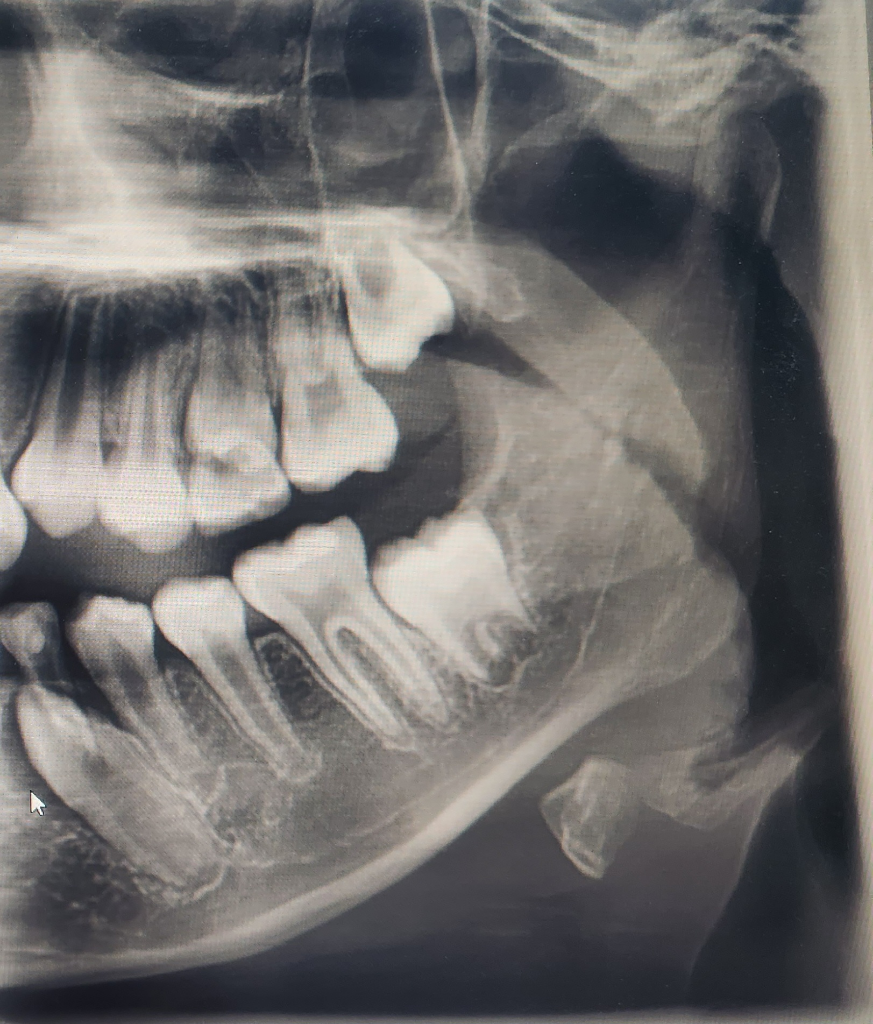

만11세이고 아래에서 왼쪽치아가 올라오고 있는데 흔들림이 없어 발치를 해주었어요

아래레서 왼쪽에 올라오고 있는 치아이고 올라오고 있음에도 유치가 흔들리지 않아 발치해 주었습니다 그리고 6개월이 지났음에도 영구치가 올라오고 있지 않아 걱정입니다

기다리면 맹출됩니다. 저정도 올라 왓으면 유치의 뿌리가 녹아서 발치를한거니 걱정하지 않으셔도 됩니다.

보통 아래 영구치의 경우 송곳니->첫번째작은어금니 -> 두번째작은어금니 순으로 앞에서부터 순서대로 유치에서 교환이 됩니다. 현재 상태는 소구치(작은어금니)2개는 다 올라와서 자리를 잡고 뿌리를 형성하고 있는 단계인데 아직 영구치 송곳니가 자리를 못잡은 상태입니다. 나오는 순서가 잘못됐다고 해서 그 자체로는 문제가 없으나 송곳니가 나올 자리 여유가 있느냐의 문제입니다. 공간이 좁아 어디에 걸려서 (locking) 나오지 못하고 있는 것일 수도 있습니다. 또한 사진상으로 명확하진 않지만 송곳니가 살짝 회전해 있는 상태인 것 같습니다. 유치 발치 후 6개월이면 지켜보는 단계는 넘어갔고 치과에서 처치가 필요해 보입니다. 공간이 없으면 나오지 못할 수도 있고 엉뚱한 곳으로 치아가 올라올 수도 있는데 이건 위 송곳니에서 종종 관찰되는 덧니 현상에 해당합니다.